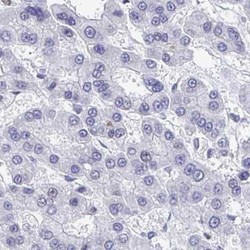

- Immunohistochemistry-Paraffin: C1qTNF10/C1qL2 Antibody [NBP2-34090] - Staining of liver cancer.

- Submitted by

- Novus Biologicals (provider)

- Main image

- Experimental details

- Immunohistochemistry-Paraffin: C1qTNF10/C1qL2 Antibody [NBP2-34090] - Staining of liver.